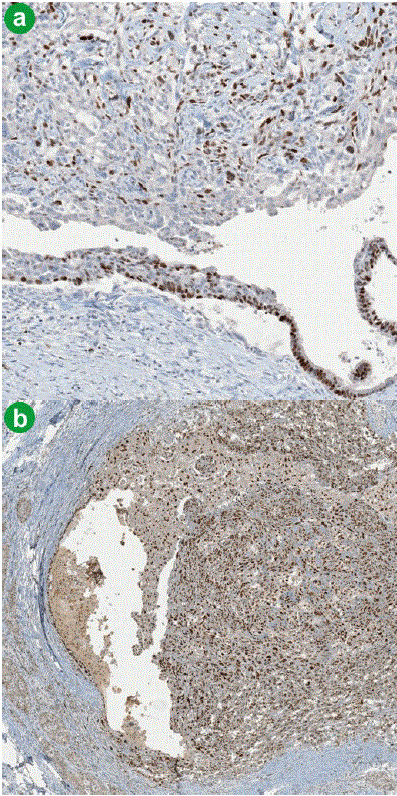

Figure 5. Intraductal growth of the undifferentiated carcinoma of the pancreas. Epithelial neoplastic component including the epithelial lining of the pancreatic duct and nonepithelial neoplastic components are positive for P63 (a. original magnification 10x) and P 53 (b. original magnification 4x).